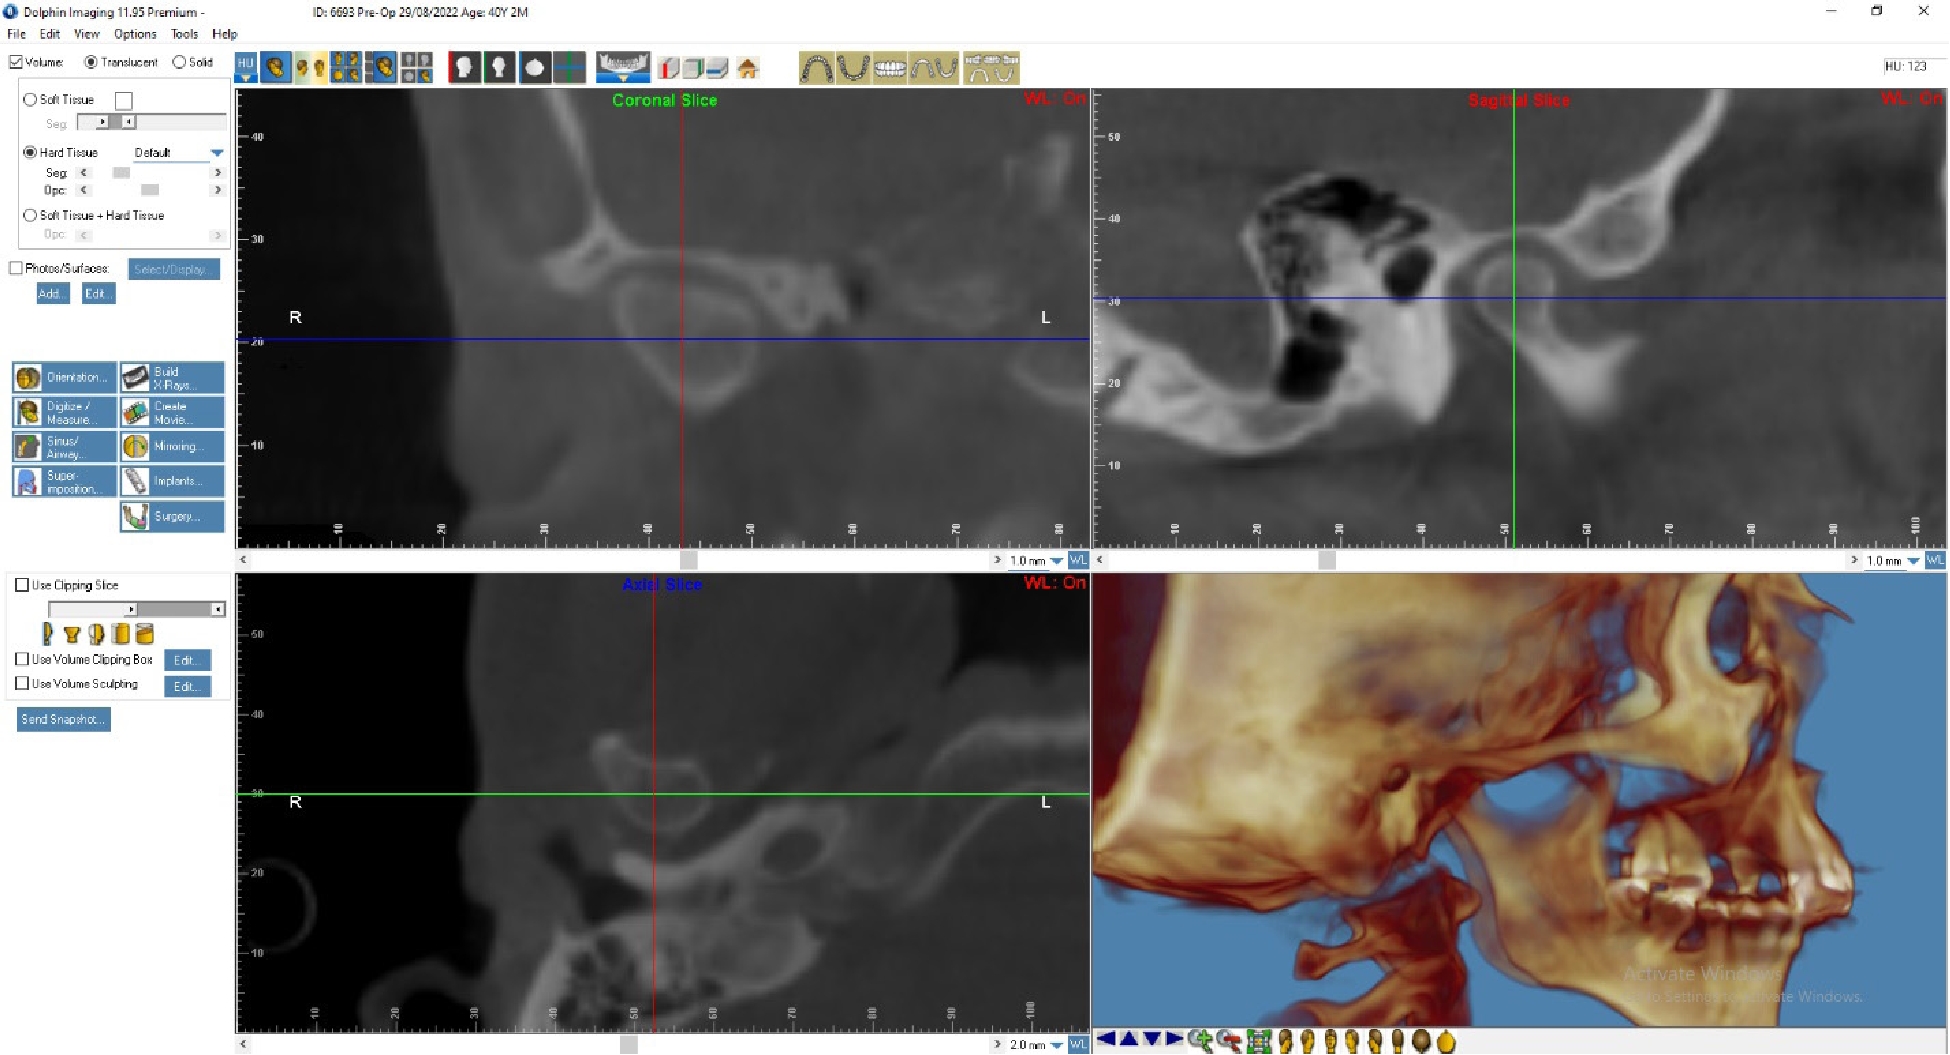

По данным МРТ ВНЧС спустя 2 года после начала лечения отмечается устранение вентро-латеральной дислокации суставного диска в положении привычной окклюзии. Также устранен синовит, увеличился объем движения в суставе (рис. 5). Как видно из рис. 4 и 5, по данным КТ ВНЧС спустя 2 года после начала лечения отмечается ремоделирование головки нижней челюсти. Клинически увеличилось открывание рта до 38 мм.

Рис. 5. Пациент Д., 40 лет. КТ ВНЧС спустя 2 года после начала лечения